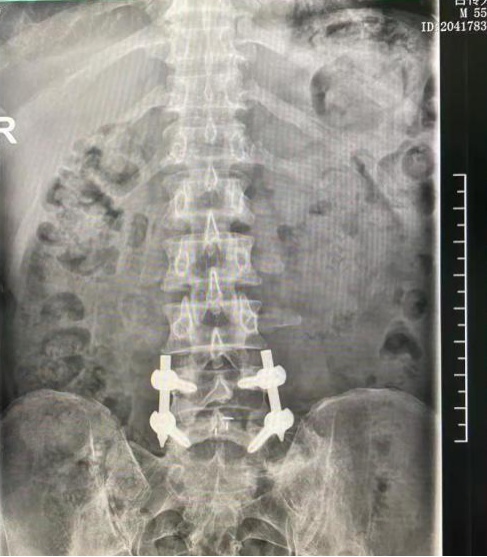

术后复查,内固定位置良好